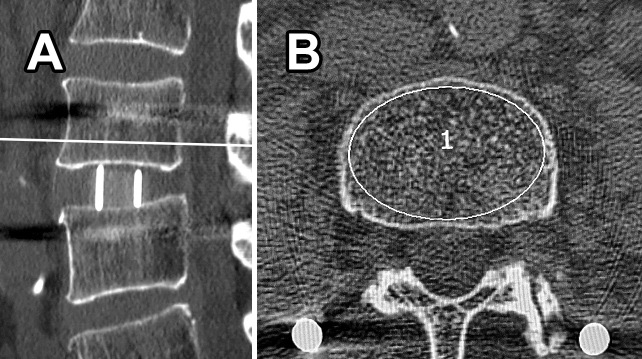

Results: TBR was commonly observed anterior to the cage on CT sagittal images. The TBR-positive rate was 21%, 67%, and 73% at 3 months, 1 year, and 2 years postoperatively, respectively. The 3-month TBR-positive segments showed significantly less VEC (0% vs. 29%, P=0.029) at 1 year postoperatively. The 1-year TBR-positive segments showed a significantly higher facet union rate (83% vs. 57%, P=0.019) and less pseudoarthrosis (0% vs. 13%, P=0.041) at 2 years postoperatively. At 5 years postoperatively, 50% of the 2-year TBR-positive segments turned negative with solid intervertebral bony fusion.

Conclusions: TBR-positive segments had significantly lower future VEC positivity, higher future facet union rates, and lower future pseudarthrosis rates. In LLIF-PSF, TBR suggests the establishment of intervertebral stability and allows consideration of intervertebral biomechanics.